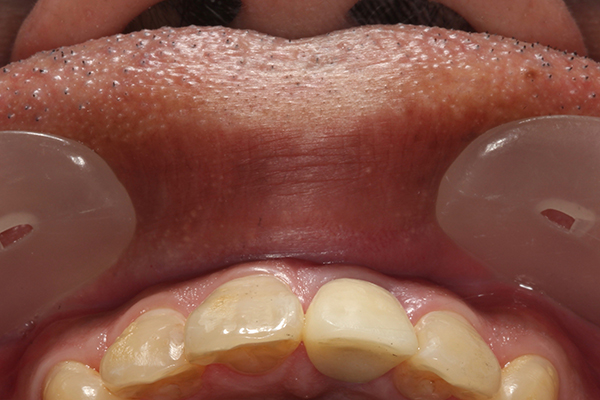

初診時とセラミッククラウンセット時の比較

左の初診時の写真と見比べるとお分かりのように、引き上げた後の右側の写真では歯ぐきの位置が適切な位置にある事がお分かりいただけるかと思います。